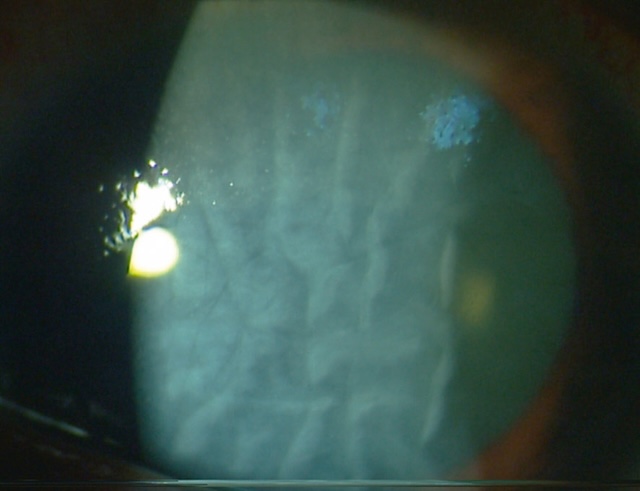

œdème cornéen et nombreux plis de la membrane de Descemet.

L’image révèle un œil avec atteinte cornéenne post-brûlure par base forte, probablement due à un produit ménager à base de soude. On observe un aspect en relief caractéristique de plis endothéliaux profonds en motif radiaire, traduisant une souffrance sévère de la couche endothéliale. La cornée centrale est opacifiée, avec un voile blanchâtre homogène, traduisant un œdème cornéen stromal persistant. La lumière incidente se réfléchit de façon diffuse, signe de la perte de transparence cornéenne. Ce tableau est typique d’une atteinte de stade avancé avec dysfonctionnement endothélial majeur consécutif à une agression alcaline.